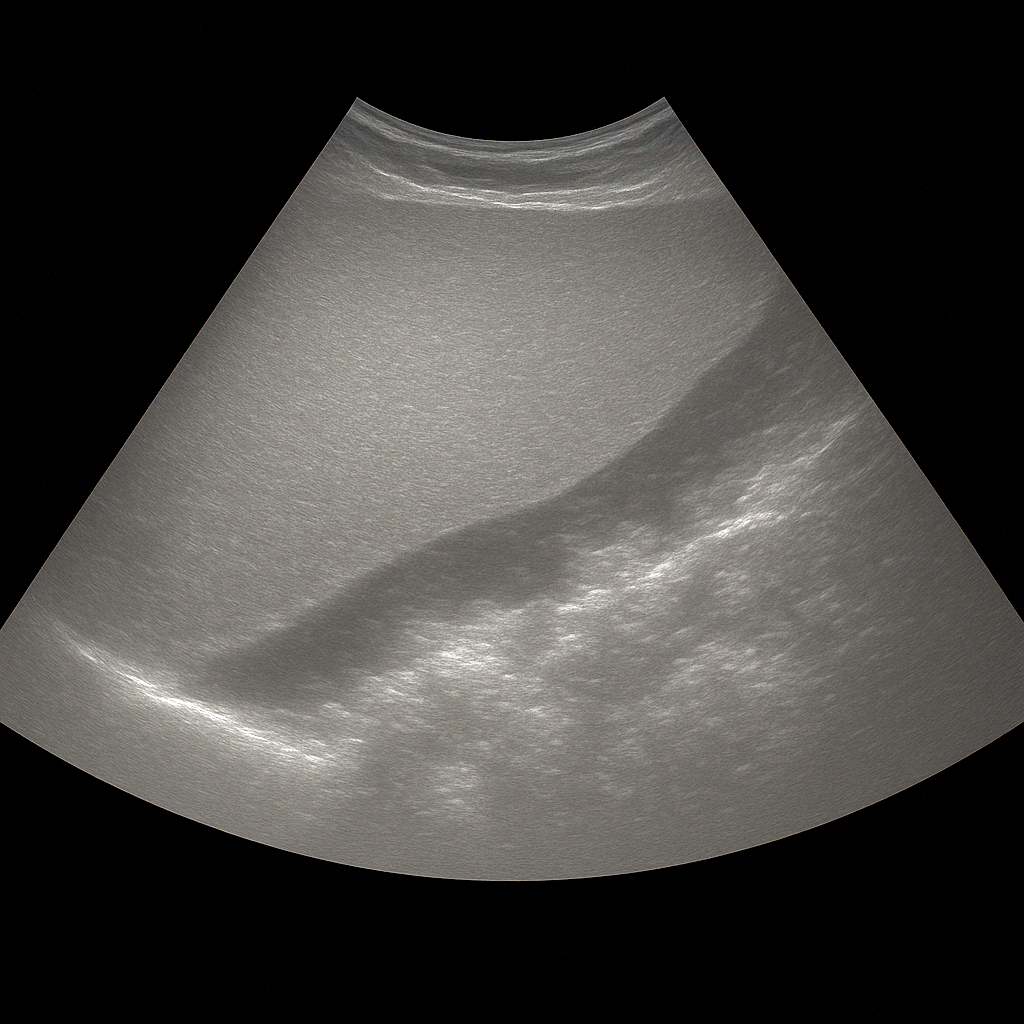

- Ultrasound of the abdomen shows the liver, gallbladder, pancreas, kidneys and other abdominal organs in real time.

- Recommended for abdominal pain, swelling, nausea or elevated liver values.

- Quick, painless and radiation-free examination of the internal organs of the abdomen.

- Written opinion and recommendation from a specialist doctor are included.